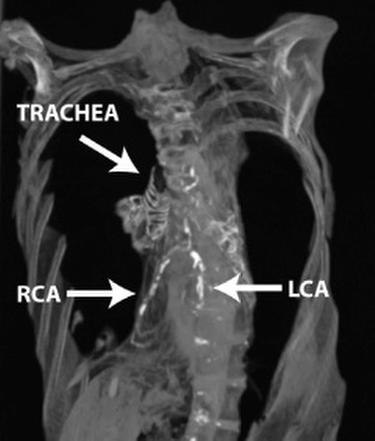

What Does Cardiac Ct Show Myheart